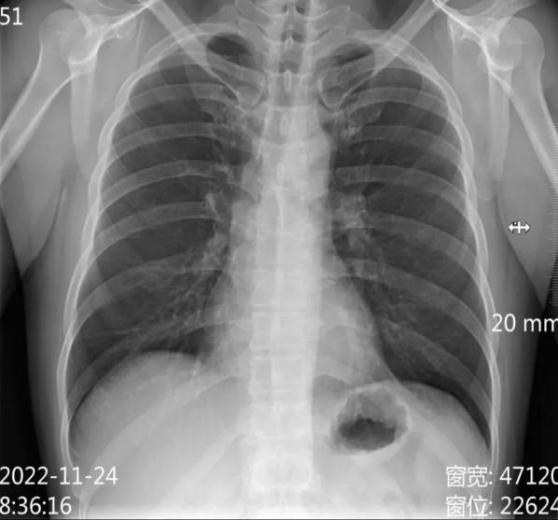

●肺部疾病筛查:如肺炎、肺结核、肺气肿等。

●初步筛查:DR是许多疾病的第一道筛查工具,尤其是肺部疾病和骨骼病变。

●快速诊断:在急诊中,DR可以帮助医生快速判断是否存在骨折、气胸等问题。

●健康管理:用于常规体检,帮助发现潜在的健康隐患。